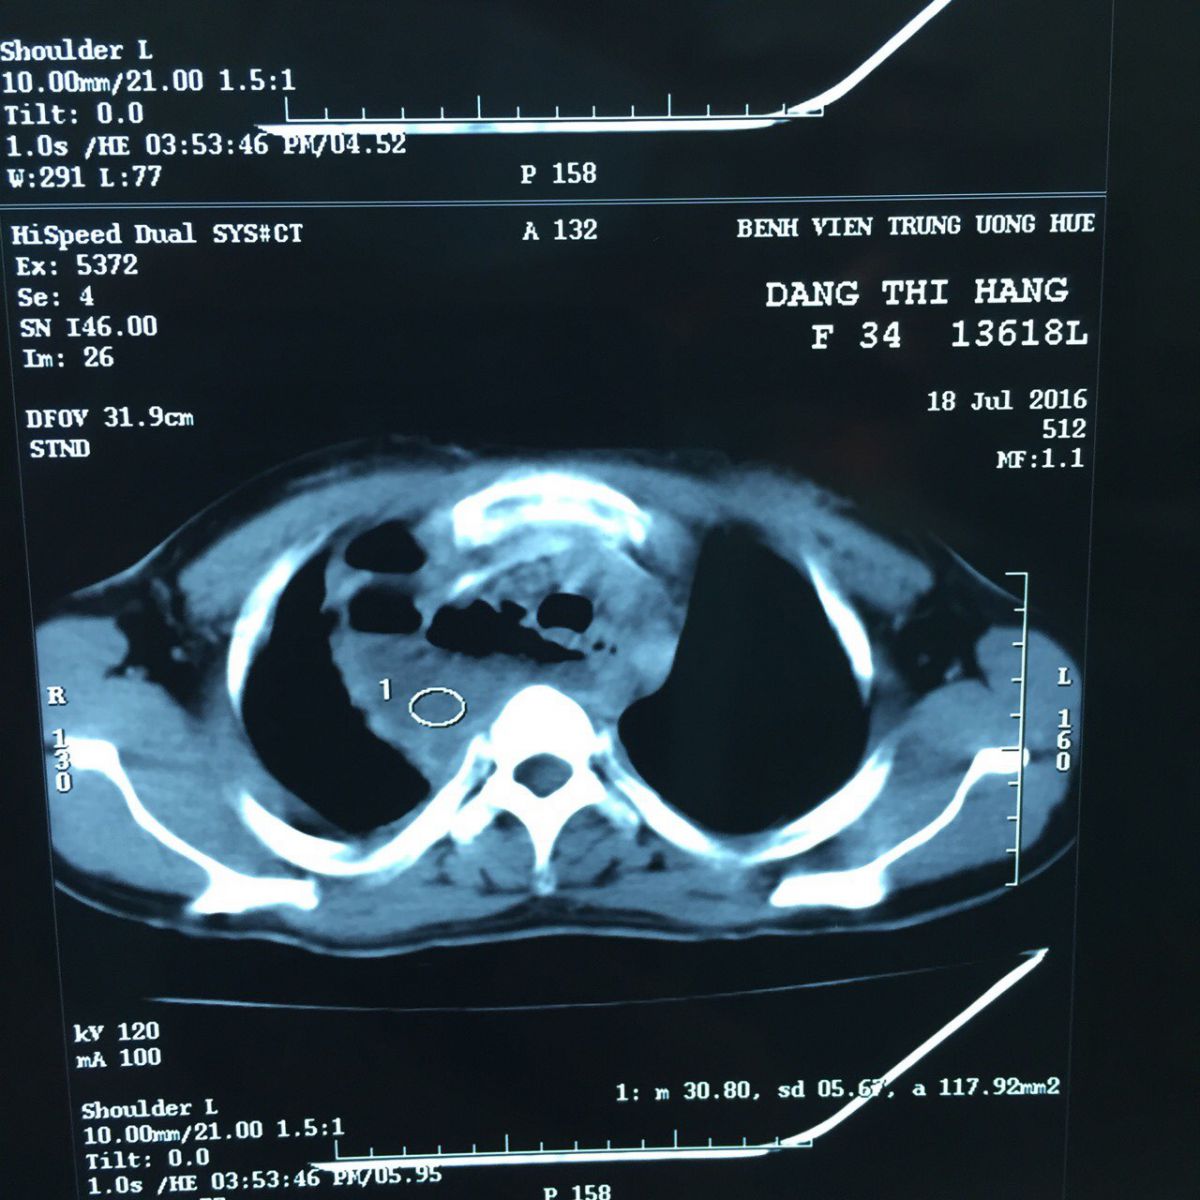

Hình ảnh áp xe trung thất trên CT Scan

Ngày 19/7, bệnh nhân Đặng Thị H. 31 tuổi nhập viện. Bệnh nhân được chuyển đến từ Bệnh viện khu vực bắc Quảng Bình trong tình trạng cấp cứu suy hô hấp, nhiễm trùng nhiễm độc nặng, cổ bạnh ra do tràn khí nhiều dưới da. Bệnh nhân được làm các xét nghiệm khẩn như: XQ phổi, siêu âm, CT scan ngực… và được PGS.TS Phạm Như Hiệp (Phó GĐ BVTW Huế, Trưởng Khoa Ngoại nhi – Cấp cứu Bụng) thăm khám trực tiếp chẩn đoán: thủng thực quản cổ bên trái gây áp xe trung thất lan rộng sau hóc xương gà, tình trạng rất nặng có thể tử vong.